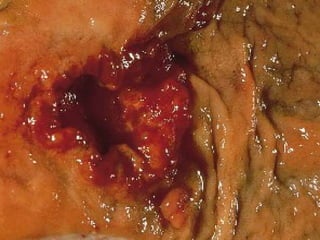

 Colonosocopia ( biopsia ).

CANCER DE COLONY RECTO PATOLOGIA  Adenocarcinoma 95%.  Carcinoides .  Carcinomas epidermoides.  2/3 colon izq. 1-3 colon derecho. 20% se localizan en recto. 3% son multicentricos y 2% desarrollan 2do. Primario.